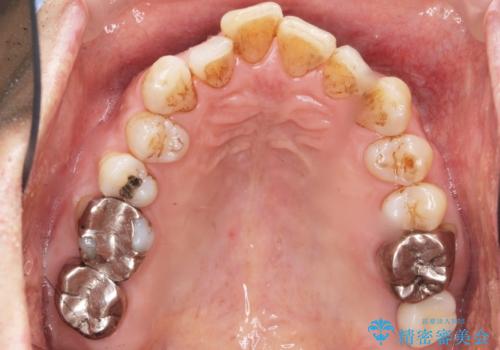

患者様のご希望により抜歯してインプラントによる治療を行いました。

上顎洞が近接しており上顎骨の厚みが薄いことから、ソケットリフト(上顎洞底挙上術)をインプラント埋入と同時に行いました。

奥歯でしっかりと咬むことができるようになり、ご満足頂けました。